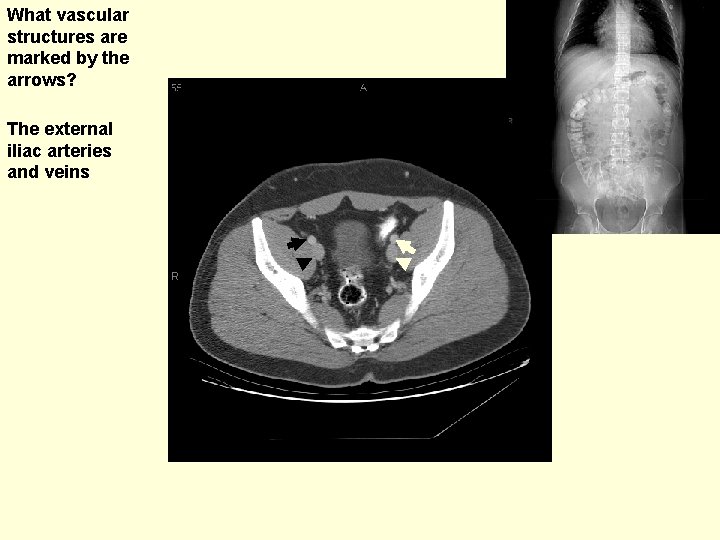

What vascular structures are marked by the arrows? The external iliac arteries and veins